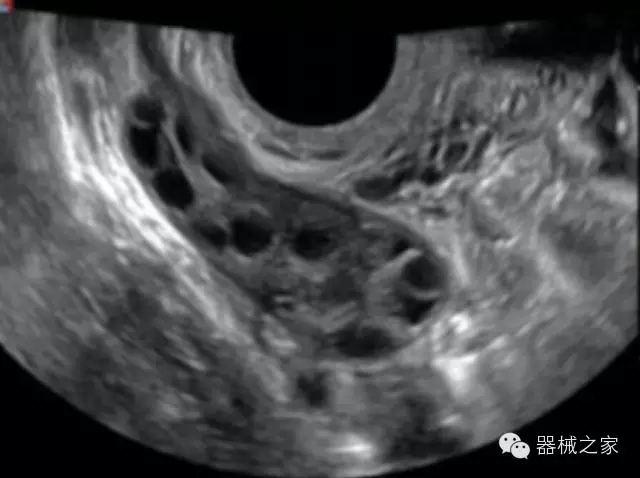

臨床圖片賞析

·高效3D/4D成像技術(shù):高速的4D幀頻,豐富的3D成像模式,智能斷層切片功能;

·獨(dú)有的大角度及實(shí)時(shí)溫控技術(shù),能同一切面顯示宮頸及宮體,有效減低了患者的痛苦,及保護(hù)粘膜保證了醫(yī)療安全;